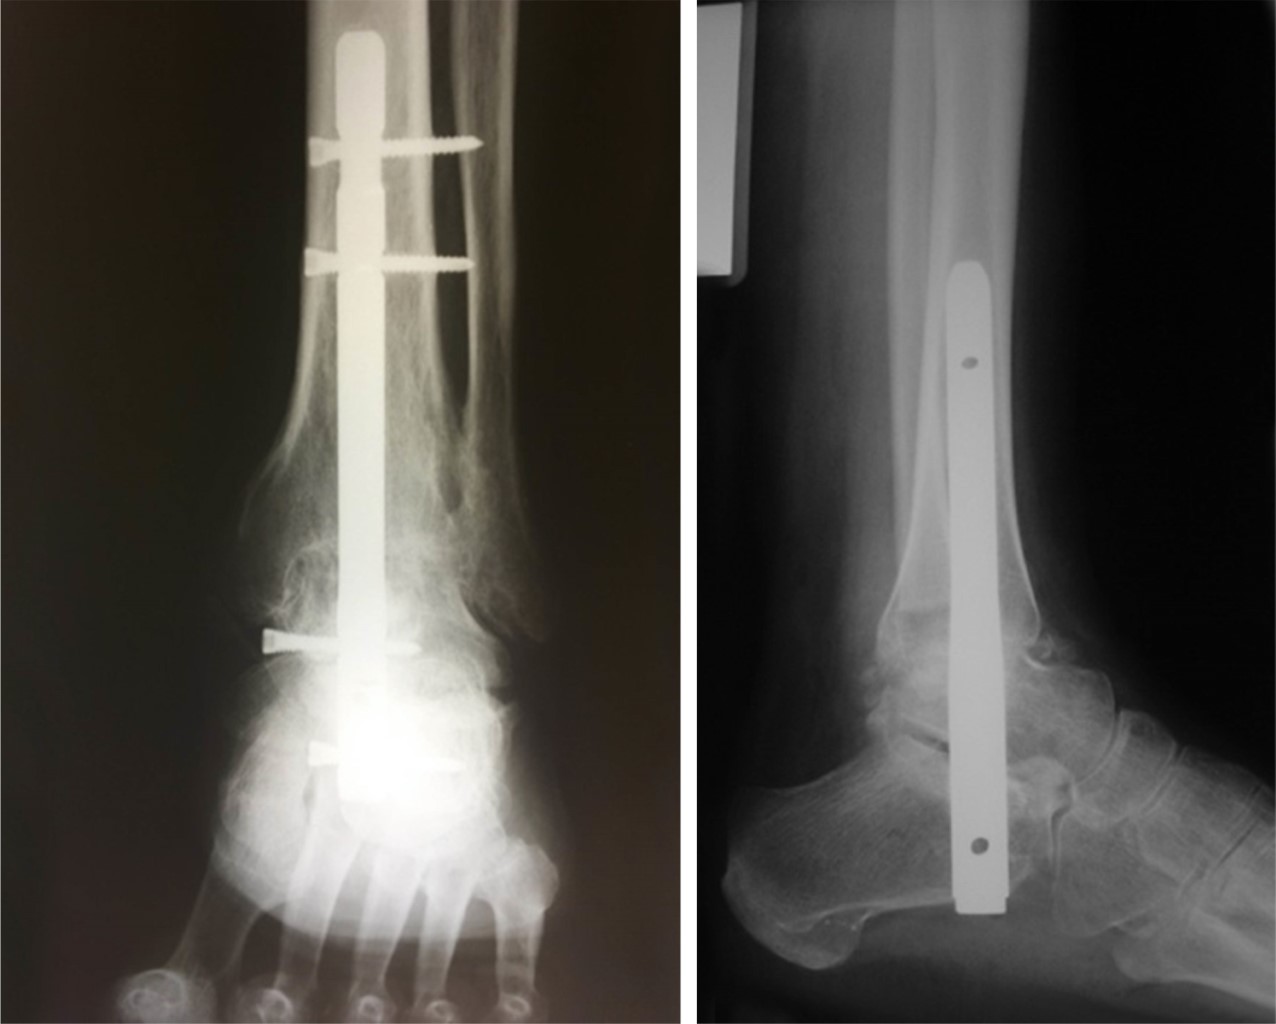

Posterior a la colocación del clavo, se verificó la posición y longitud con el intensificador de imágenes, se realizó el bloqueo posterior y después los bloqueos mediales, se verificó la posición de los mismos y se suturó por planos (Figura 3).

A las ocho semanas se valora control radiográfico, se retira la bota para baño y descanso y se utiliza para la deambulación por cuatro semanas, se retira y se toma control postquirúrgico (Figura 5).

Figura 3

Figura 5